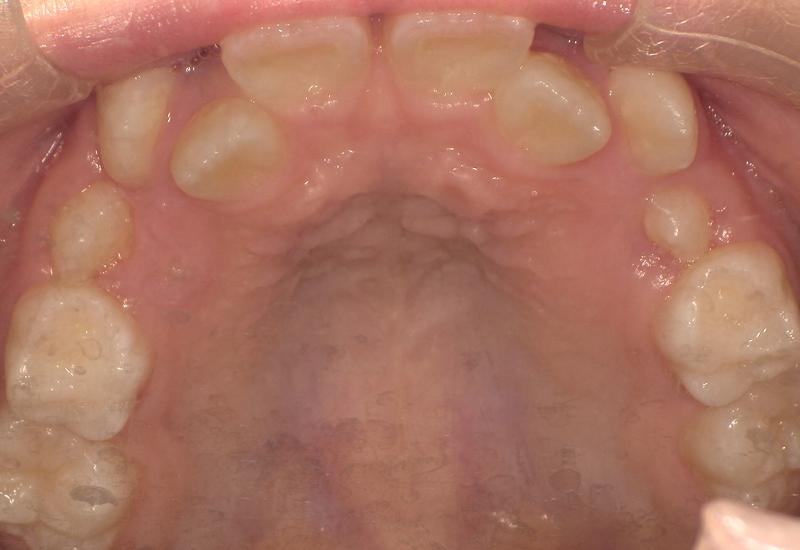

症例② シェイプメモリーアライナーによる混合歯列期の矯正

治療期間 6ヶ月

治療時の年齢/性別 10歳 / 女性

かかった治療費 440,000円

治療方法 シェイプメモリーアライナー

注意点・リスク 今、現在萌えてきている永久歯を動かす為、なるべく早く治療を終了させる